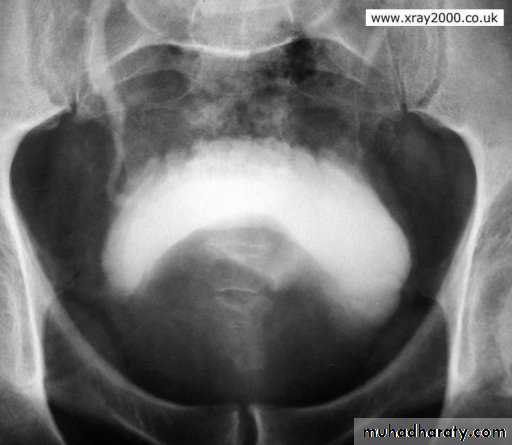

IVU: elevation of bladder base, irregular bladder out line, bladder diverticulum, fish hook lower ureter, vesical stones and residual urine.

Benign prostatic hyperplasia

Vesical stone